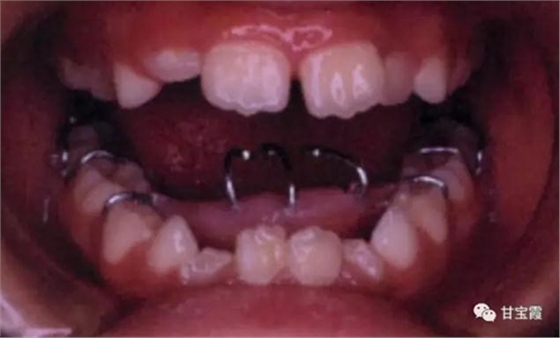

家長發(fā)現(xiàn)孩子嘴型不好看,吃東西也咬不斷,就帶著孩子找我看診,經(jīng)過檢查和診斷,我決定給孩子戴個舌刺,讓孩子的舌頭舔不著下前牙,如下圖